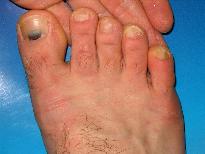

Foto 1. Eritem pelagroid, pacienta in virsta de 45 de ani, alcoolica de aproximativ 7 ani. |

Foto 10. Pacient 25 de ani, internat pt etilism acut. La examenul fizic se evidentiaza onocomicoza incipenta dg. V ambe picioara si marci traumatice (hematoame subunghiale) la halucele drept si dg. III picior sting. Anamneza amanuntita si aplicarea chestionarelor incadreaza pacientul in clasa dependentilor cronici de alcool. |